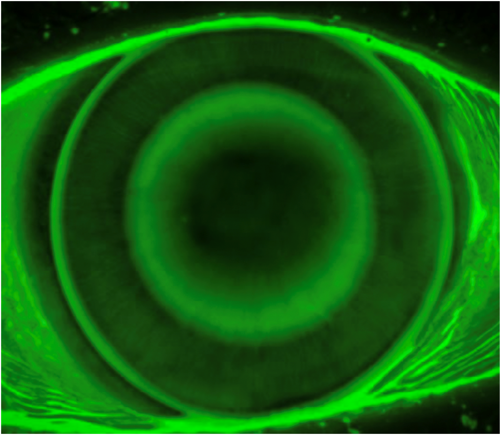

At the dispense visit, the lenses were placed on each eye. Visual acuity was 20/20 through each lens, and over-refraction yielded 20/20 with +0.75 OD and OS. Fluorescein pattern assessment showed an aligned central treatment zone with a centered bullseye ring and aligned peripheral curves. There was mild edge lift and adequate movement on blink to promote tear exchange. The lens fit was deemed acceptable in both eyes, and lenses were dispensed after the patient received training on lens care and handling.